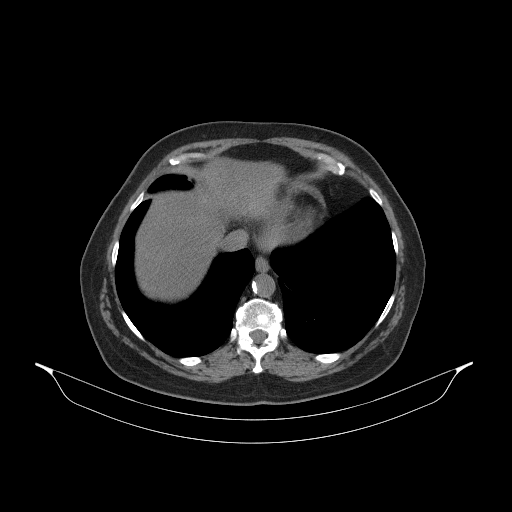

Generated VENOUS CT scan (A→B translation)

Full window (WL 1023.5, WW 4095 β†’ Low βˆ’1024, High +3071)

Mediastinum window (WL 40, WW 400 β†’ Low βˆ’160, High +240)